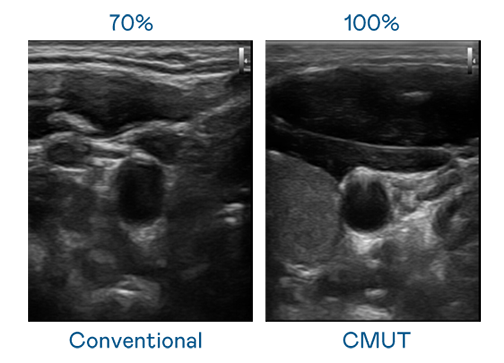

CMUT 技术是一种用电容式微机电元件来产生超音波讯号的技术。与传统 PZT 压电式技术相比,CMUT 频宽增加 30%,更宽频的超音波讯号让影像解析度大幅提升,是实现高影像品质医疗超音波扫描、促进精准医疗发展的关键技术。

大频宽带来超清晰影像

超音波影像的解析度高低,首先取决于探头能发出的讯号频宽。英国上市公司365 CMUT 可提供高清晰的超音波讯号,提供高频宽、高灵敏度、影像纹理细节更高的超音波影像,协助医护人员缩短影像判读时间及利用精准的医疗影像进行诊断。